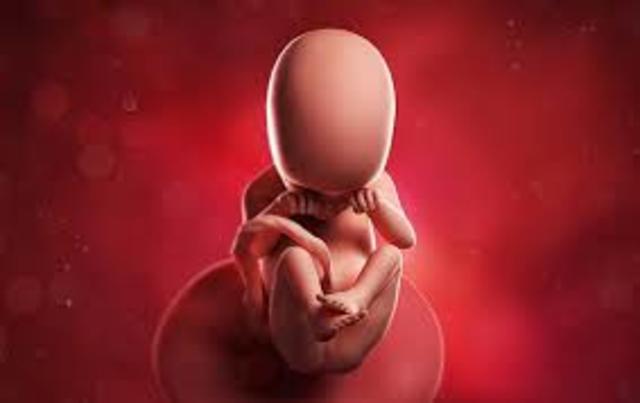

• SEMANA 27-30

SEMANA 27-30

El cerebro del bebé crece rápidamente.

El sistema nervioso se desarrolla lo suficiente para controlar algunas funciones del cuerpo.

Los párpados del bebé se pueden abrir y cerrar.

El aparato respiratorio, aunque inmaduro, produce agente tensioactivo. Esta sustancia ayuda a que los alvéolos se llenen de aire.

Los huesos del cráneo tienen una característica: están separados entre sí por surcos de tejido conectivo, las suturas